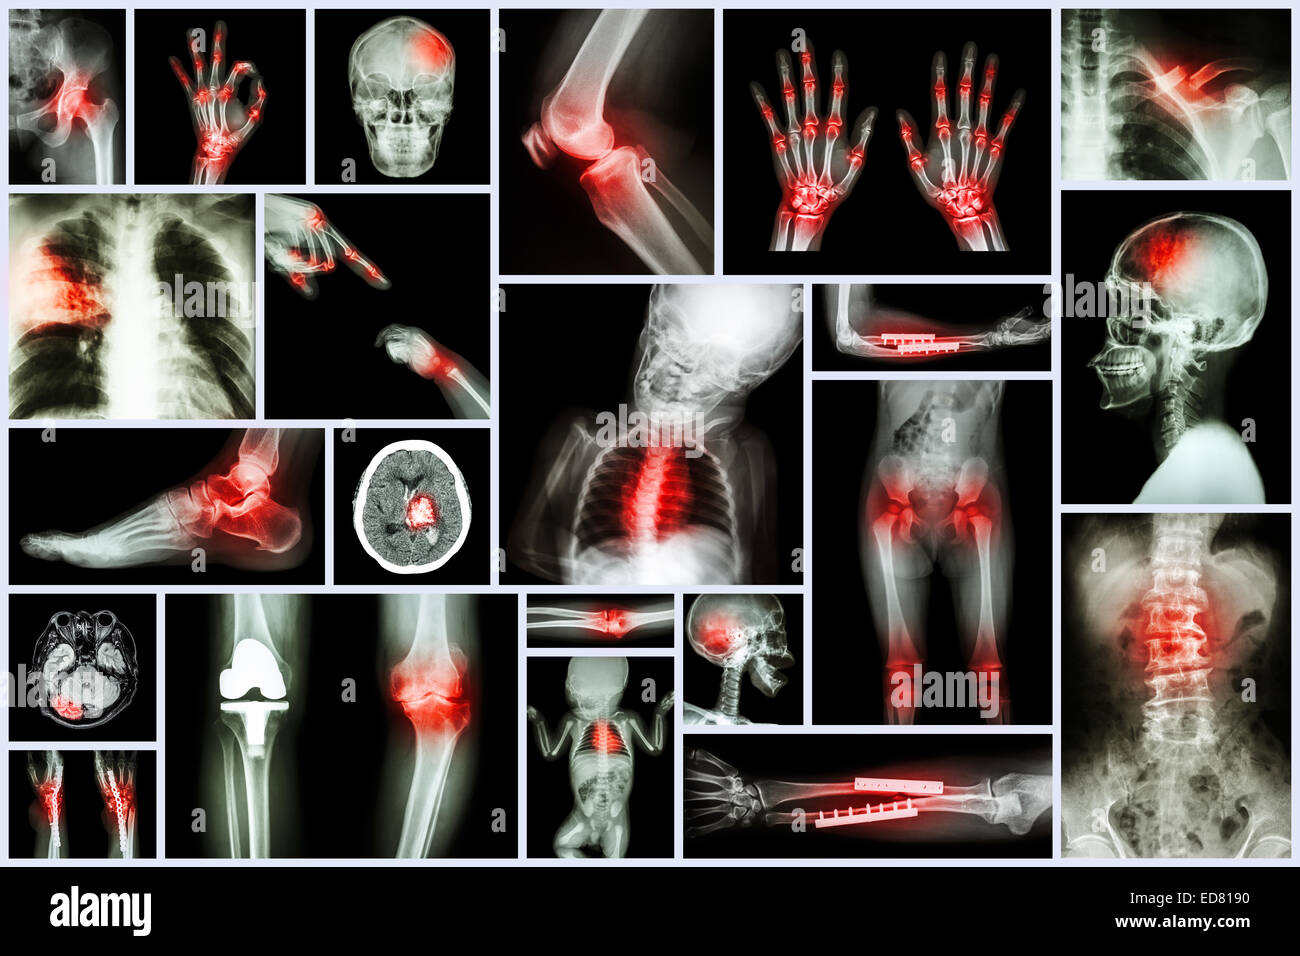

Collection X-ray et d'organes multiples à l'arthrite rhumatoïde (commune de multiples,la goutte) Banque D'Imageshttps://www.alamyimages.fr/image-license-details/?v=1https://www.alamyimages.fr/photo-image-collection-x-ray-et-d-organes-multiples-a-l-arthrite-rhumatoide-commune-de-multiples-la-goutte-77392076.html

Collection X-ray et d'organes multiples à l'arthrite rhumatoïde (commune de multiples,la goutte) Banque D'Imageshttps://www.alamyimages.fr/image-license-details/?v=1https://www.alamyimages.fr/photo-image-collection-x-ray-et-d-organes-multiples-a-l-arthrite-rhumatoide-commune-de-multiples-la-goutte-77392076.htmlRFEDWEAM–Collection X-ray et d'organes multiples à l'arthrite rhumatoïde (commune de multiples,la goutte)

Collection X-ray et d'organes multiples à l'arthrite rhumatoïde (commune de multiples,la goutte) Banque D'Imageshttps://www.alamyimages.fr/image-license-details/?v=1https://www.alamyimages.fr/photo-image-collection-x-ray-et-d-organes-multiples-a-l-arthrite-rhumatoide-commune-de-multiples-la-goutte-77392073.html

Collection X-ray et d'organes multiples à l'arthrite rhumatoïde (commune de multiples,la goutte) Banque D'Imageshttps://www.alamyimages.fr/image-license-details/?v=1https://www.alamyimages.fr/photo-image-collection-x-ray-et-d-organes-multiples-a-l-arthrite-rhumatoide-commune-de-multiples-la-goutte-77392073.htmlRFEDWEAH–Collection X-ray et d'organes multiples à l'arthrite rhumatoïde (commune de multiples,la goutte)

Ensemble de plusieurs rayons-X de la maladie,Plusieurs,chirurgie orthopédique,course,(fracture des os,opération orthopédique,calcul rénal, Banque D'Imageshttps://www.alamyimages.fr/image-license-details/?v=1https://www.alamyimages.fr/photo-image-ensemble-de-plusieurs-rayons-x-de-la-maladie-plusieurs-chirurgie-orthopedique-course-fracture-des-os-operation-orthopedique-calcul-renal-77404872.html

Ensemble de plusieurs rayons-X de la maladie,Plusieurs,chirurgie orthopédique,course,(fracture des os,opération orthopédique,calcul rénal, Banque D'Imageshttps://www.alamyimages.fr/image-license-details/?v=1https://www.alamyimages.fr/photo-image-ensemble-de-plusieurs-rayons-x-de-la-maladie-plusieurs-chirurgie-orthopedique-course-fracture-des-os-operation-orthopedique-calcul-renal-77404872.htmlRFEDX2KM–Ensemble de plusieurs rayons-X de la maladie,Plusieurs,chirurgie orthopédique,course,(fracture des os,opération orthopédique,calcul rénal,

Collection X-ray partie multiples des droits de l'arthrite et la goutte (maladie,plusieurs , la polyarthrite rhumatoïde, la maladie de coeur congénitale,course) Banque D'Imageshttps://www.alamyimages.fr/image-license-details/?v=1https://www.alamyimages.fr/photo-image-collection-x-ray-partie-multiples-des-droits-de-l-arthrite-et-la-goutte-maladie-plusieurs-la-polyarthrite-rhumatoide-la-maladie-de-coeur-congenitale-course-77404848.html

Collection X-ray partie multiples des droits de l'arthrite et la goutte (maladie,plusieurs , la polyarthrite rhumatoïde, la maladie de coeur congénitale,course) Banque D'Imageshttps://www.alamyimages.fr/image-license-details/?v=1https://www.alamyimages.fr/photo-image-collection-x-ray-partie-multiples-des-droits-de-l-arthrite-et-la-goutte-maladie-plusieurs-la-polyarthrite-rhumatoide-la-maladie-de-coeur-congenitale-course-77404848.htmlRFEDX2JT–Collection X-ray partie multiples des droits de l'arthrite et la goutte (maladie,plusieurs , la polyarthrite rhumatoïde, la maladie de coeur congénitale,course)

Collection X-ray des multiples d'organes et la chirurgie orthopédique et de multiples maladies (tuberculose pulmonaire , la goutte, l'arth Banque D'Imageshttps://www.alamyimages.fr/image-license-details/?v=1https://www.alamyimages.fr/photo-image-collection-x-ray-des-multiples-d-organes-et-la-chirurgie-orthopedique-et-de-multiples-maladies-tuberculose-pulmonaire-la-goutte-l-arth-77008650.html

Collection X-ray des multiples d'organes et la chirurgie orthopédique et de multiples maladies (tuberculose pulmonaire , la goutte, l'arth Banque D'Imageshttps://www.alamyimages.fr/image-license-details/?v=1https://www.alamyimages.fr/photo-image-collection-x-ray-des-multiples-d-organes-et-la-chirurgie-orthopedique-et-de-multiples-maladies-tuberculose-pulmonaire-la-goutte-l-arth-77008650.htmlRFED818X–Collection X-ray des multiples d'organes et la chirurgie orthopédique et de multiples maladies (tuberculose pulmonaire , la goutte, l'arth

Collection X-ray des multiples d'organes et la chirurgie orthopédique et de multiples maladies (tuberculose pulmonaire , la goutte, l'arth Banque D'Imageshttps://www.alamyimages.fr/image-license-details/?v=1https://www.alamyimages.fr/photo-image-collection-x-ray-des-multiples-d-organes-et-la-chirurgie-orthopedique-et-de-multiples-maladies-tuberculose-pulmonaire-la-goutte-l-arth-77008652.html

Collection X-ray des multiples d'organes et la chirurgie orthopédique et de multiples maladies (tuberculose pulmonaire , la goutte, l'arth Banque D'Imageshttps://www.alamyimages.fr/image-license-details/?v=1https://www.alamyimages.fr/photo-image-collection-x-ray-des-multiples-d-organes-et-la-chirurgie-orthopedique-et-de-multiples-maladies-tuberculose-pulmonaire-la-goutte-l-arth-77008652.htmlRFED8190–Collection X-ray des multiples d'organes et la chirurgie orthopédique et de multiples maladies (tuberculose pulmonaire , la goutte, l'arth

X-ray plusieurs partie de la avec de multiples maladies (accident vasculaire cérébral, l'arthrite, la goutte, le rhumatisme, tumeur au cerveau, l'arthrose, etc.) Banque D'Imageshttps://www.alamyimages.fr/image-license-details/?v=1https://www.alamyimages.fr/photo-image-x-ray-plusieurs-partie-de-la-avec-de-multiples-maladies-accident-vasculaire-cerebral-l-arthrite-la-goutte-le-rhumatisme-tumeur-au-cerveau-l-arthrose-etc-77391487.html

X-ray plusieurs partie de la avec de multiples maladies (accident vasculaire cérébral, l'arthrite, la goutte, le rhumatisme, tumeur au cerveau, l'arthrose, etc.) Banque D'Imageshttps://www.alamyimages.fr/image-license-details/?v=1https://www.alamyimages.fr/photo-image-x-ray-plusieurs-partie-de-la-avec-de-multiples-maladies-accident-vasculaire-cerebral-l-arthrite-la-goutte-le-rhumatisme-tumeur-au-cerveau-l-arthrose-etc-77391487.htmlRFEDWDHK–X-ray plusieurs partie de la avec de multiples maladies (accident vasculaire cérébral, l'arthrite, la goutte, le rhumatisme, tumeur au cerveau, l'arthrose, etc.)

X-ray plusieurs partie de la avec de multiples maladies (accident vasculaire cérébral, l'arthrite, la goutte, le rhumatisme, tumeur au cerveau, l'arthrose, etc.) Banque D'Imageshttps://www.alamyimages.fr/image-license-details/?v=1https://www.alamyimages.fr/photo-image-x-ray-plusieurs-partie-de-la-avec-de-multiples-maladies-accident-vasculaire-cerebral-l-arthrite-la-goutte-le-rhumatisme-tumeur-au-cerveau-l-arthrose-etc-77391482.html

X-ray plusieurs partie de la avec de multiples maladies (accident vasculaire cérébral, l'arthrite, la goutte, le rhumatisme, tumeur au cerveau, l'arthrose, etc.) Banque D'Imageshttps://www.alamyimages.fr/image-license-details/?v=1https://www.alamyimages.fr/photo-image-x-ray-plusieurs-partie-de-la-avec-de-multiples-maladies-accident-vasculaire-cerebral-l-arthrite-la-goutte-le-rhumatisme-tumeur-au-cerveau-l-arthrose-etc-77391482.htmlRFEDWDHE–X-ray plusieurs partie de la avec de multiples maladies (accident vasculaire cérébral, l'arthrite, la goutte, le rhumatisme, tumeur au cerveau, l'arthrose, etc.)